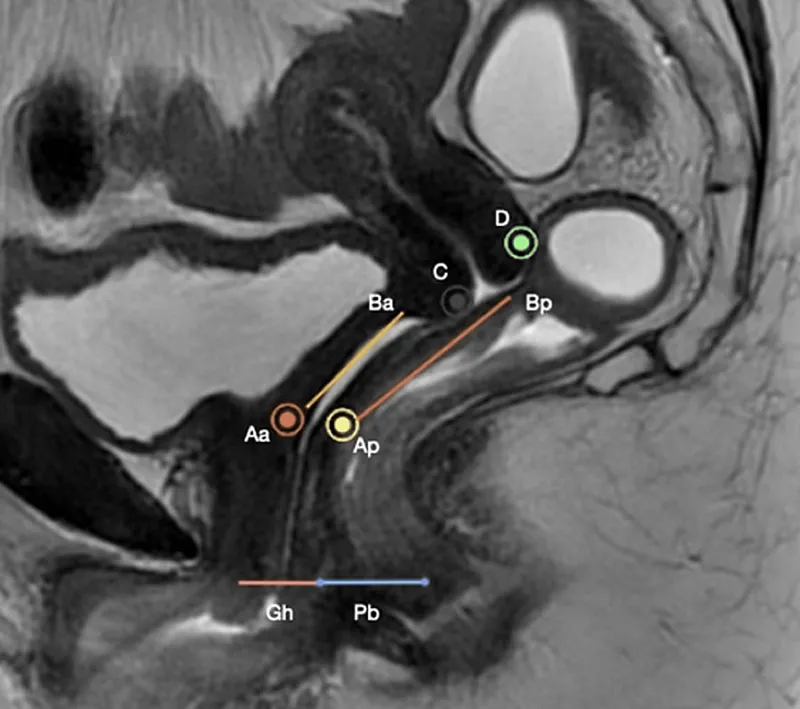

- Staging Systems:

- POP-Q (Pelvic Organ Prolapse Quantification): Standard, objective. Point Bp (most distal point on posterior vaginal wall) is key for rectocele.

- Stage 0: No prolapse.

- Stage I: Leading edge >1 cm above hymen (value < -1 cm).

- Stage II: Leading edge between -1 cm and +1 cm relative to hymen.

- Stage III: Leading edge >1 cm below hymen, but < (TVL-2) cm. (TVL = Total Vaginal Length)

- Stage IV: Complete eversion; leading edge ≥ (TVL-2) cm.

- Baden-Walker System: Simpler, less precise (Grades 0-4).

⭐ Enterocele typically involves the herniation of the small bowel and is often found superior and posterior to a rectocele; it may become more apparent when the patient is standing or straining.

- POP-Q system is crucial for objective assessment and staging.